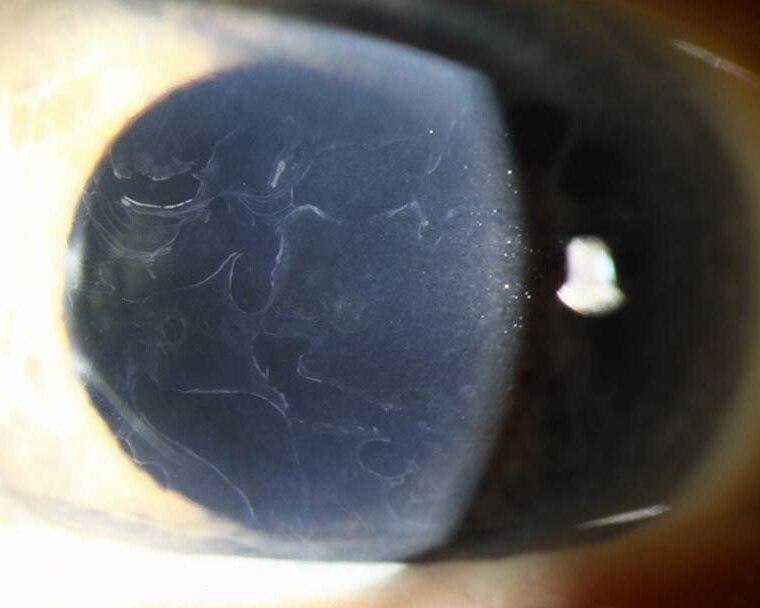

파란색 영역: 상피 내 기저막 물질이 존재하는 부분

하늘색 영역: 상피 내 기저막 물질이 부족한 부분

초록색 점: 괴사핵과 세포질 잔해를 포함한 상피 내 낭포 (Intraepithelial cyst)로서 dot으로 불립니다.

노란색 선 : map은 각막상피내에 상피바닥막이 침투된 형태로, 상피바닥막 침투가 있는 부분과 없는 부분이 모인 형태입니다.

finger print 는 상피 바닥막이 상피내에서 여러줄 평행하게 보이는것입니다.

이처럼 map, dot, finger print 의 형태로 보이기에 map dot finger print dystrophy 라고 합니다.